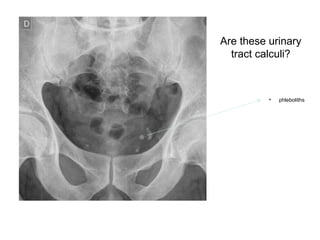

Are these urinary

tract calculi?

• phleboliths

Are these urinary tractcalculi? • phleboliths